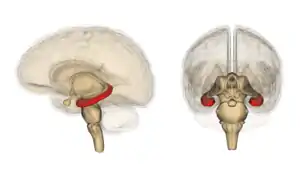

![]() El hipocampo está localizado en la parte medial del lóbulo temporal del cerebro. En esta vista lateral del cerebro humano, el lóbulo frontal está a la izquierda, el lóbulo occipital a la derecha, y los lóbulos temporal y parietal han sido retirados en gran medida para revelar el hipocampo subyacente. | ||

El hipocampo en su conjunto tiene forma de un tubo curvado, cuyo aspecto recordó a los anatomistas formas tan variadas como la del caballito de mar, el cuerno de un carnero o del dios Amón (el Cornu Ammonis actualmente designa una parte del hipocampo que comprende las divisiones entre CA1 y CA4), y también una banana.[29] Comprende porciones ventrales y dorsales, compartiendo ambas una composición similar, pero siendo partes de diferentes circuitos neurales.[31]

Este esquema general se mantiene a lo largo de todo el rango de especies de mamíferos, desde el erizo a los humanos, aunque los detalles varían. En ratas, los dos hipocampos recuerdan por su forma a bananas unidas por su tallo, mientras que en el cerebro de primates o el humano, la porción del hipocampo que se encuentra hacia el fondo, cerca de la base del lóbulo temporal, es mucho más ancha que la de la parte superior. Una de las consecuencias de esta compleja geometría es que las secciones cruzadas a través del hipocampo pueden adoptar una gran variedad de formas dependiendo del ángulo de localización del corte.